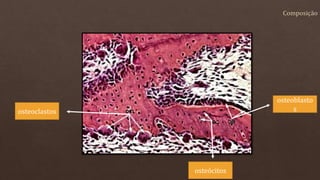

O documento lista os números de vértebras de diferentes animais e descreve as células e estruturas ósseas, incluindo osteoblastos, osteoclastos, matriz óssea mineralizada e não mineralizada. Também menciona a diferenciação de células mesenquimatosas em osteoblastos que secretam a matriz óssea.